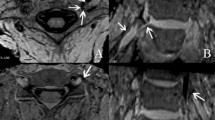

All unenhanced MRI scans of the lumbar spine for the present study were acquired using a Magnetom Aera 1.5 T MRI scanner (Siemens, Erlangen, Germany) with an integrated spine coil. In addition to the standard protocol of a conventional sagittal T1-weighted turbo spin-echo sequence (T1W-TSE), sagittal, axial, and oblique-coronal T2W-TSE, and parasagittal 3D-CISS sequences were performed. The detectability of the IFLs was evaluated using the acquired CISS image series for each patient. For the present study, we predetermined that only the right-sided neuroforamina of the lumbar spine would be examined with the additional sequences (3D-CISS), as the feasibility of IFL imaging was the primary concern. To accurately depict the anatomical course of the neuroforamen, the oblique-coronal T2W series was first aligned orthogonally with the long axis of the lumbar lordosis as best as possible. The parasagittal 3D-CISS sequence was then aligned using the oblique-coronal and axial T2W images. Figure 1 illustrates the planning of the image slices. Figure 2 shows an example of lumbar IF images created using the CISS sequence. The 3D-CISS sequence used the following parameters: slice thickness, 1 mm; repetition time/echo time (TR/TE), 5.81/2.51 ms; voxel size, 0.3 mm3; field of view (FOV), 180 mm; flip angle, 70°; and acquisition time, 3 min 59 s.

Axial T2-weighted magnetic resonance imaging (MRI) for planning the parasagittal constructive interference in steady state (CISS) sequence at the level of the nerve root; the slices were aligned perpendicularly to the course of the intervertebral foramen; incidental right paramedian vertebral body hemangiomas

Sagittal magnetic resonance imaging (MRI) three-dimensional (3D) constructive interference in steady state (CISS) sequence of a 66 year-old male proband: the lumbar spine is seen from the vertebral body L1 to L3; a and b, as well as c and d, are consecutive slices; the inferior intervertebral ligament is highlighted with an arrow, and the small vessels are marked with white stars